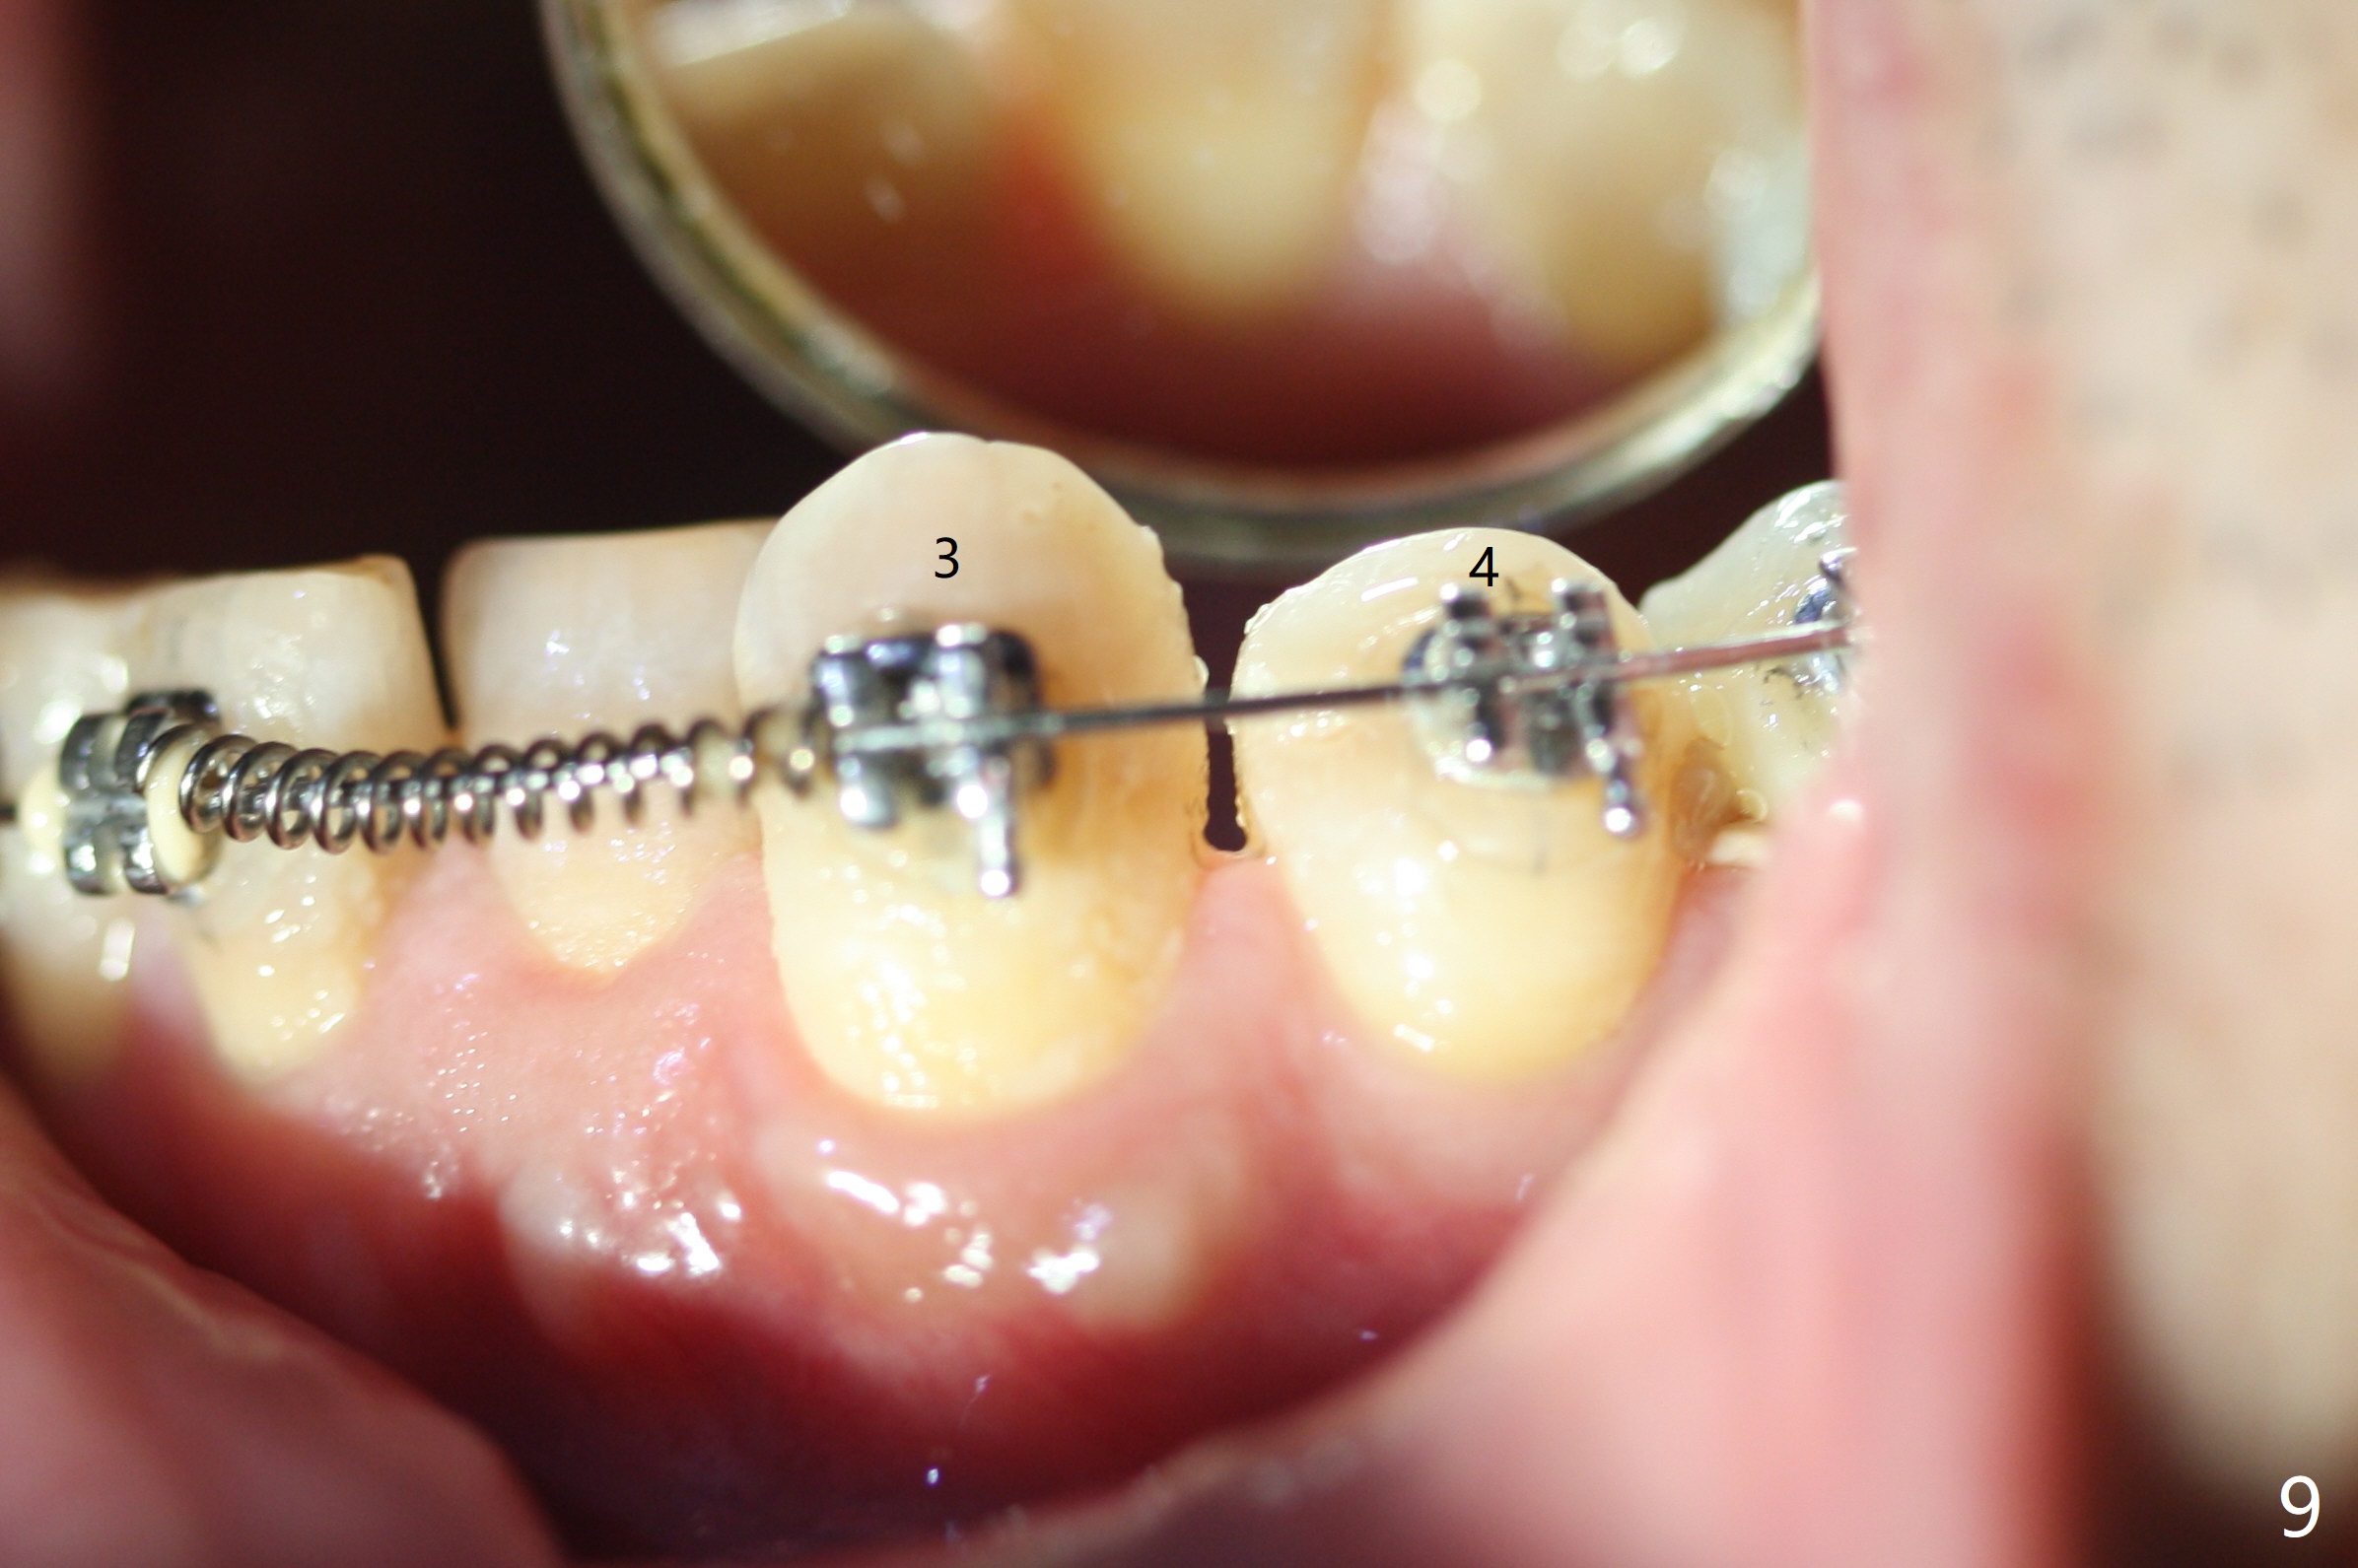

Two weeks post provisionalization over implants at #18 and 19 (4.5 months postop), acrylic is added to the provisional (Fig.1 *) and composite is placed on the other side (Fig.2 *) for clearance (Fig.3). Six days post bracketing, the diastema between LL5 and 6 decreases (Fig.4 between arrows, as compared to Fig.3), suggesting uprighting and distalization of the affected tooth. The diastema increases by trimming the mesial surface of LL6 provisional (Fig.5 *) prior to power chain placement. More acrylic is added to the occlusal surface of LL 6 and 7; more composite to that of UR3 (as compared to Fig.2) for clearance. Power chains change every week. LL5 is uprighted and distalized 1.5 months post banding (Fig.6,7 (14 niti)). Anterior brackets will be placed to correct LL2 cross bite next visit. Three weeks post open coil spring (5 months post initial banding), there is a space between LL2 and 3 (Fig.8) and between LL3/4 (Fig.9). The latter reduces instantly post power chain between LL3 and 6 (Fig.10). There is enough space for LL2 and sling shot is used to correct the cross bite 6.5 months post initial banding (Fig.11). The cross bite is corrected in 1.5 months after occlusal clearance is established (Fig.12). The lower left alignment is within normal limit, although in cross bite with the opposing dentition, immediate post molar crown cementation (Fig.13).